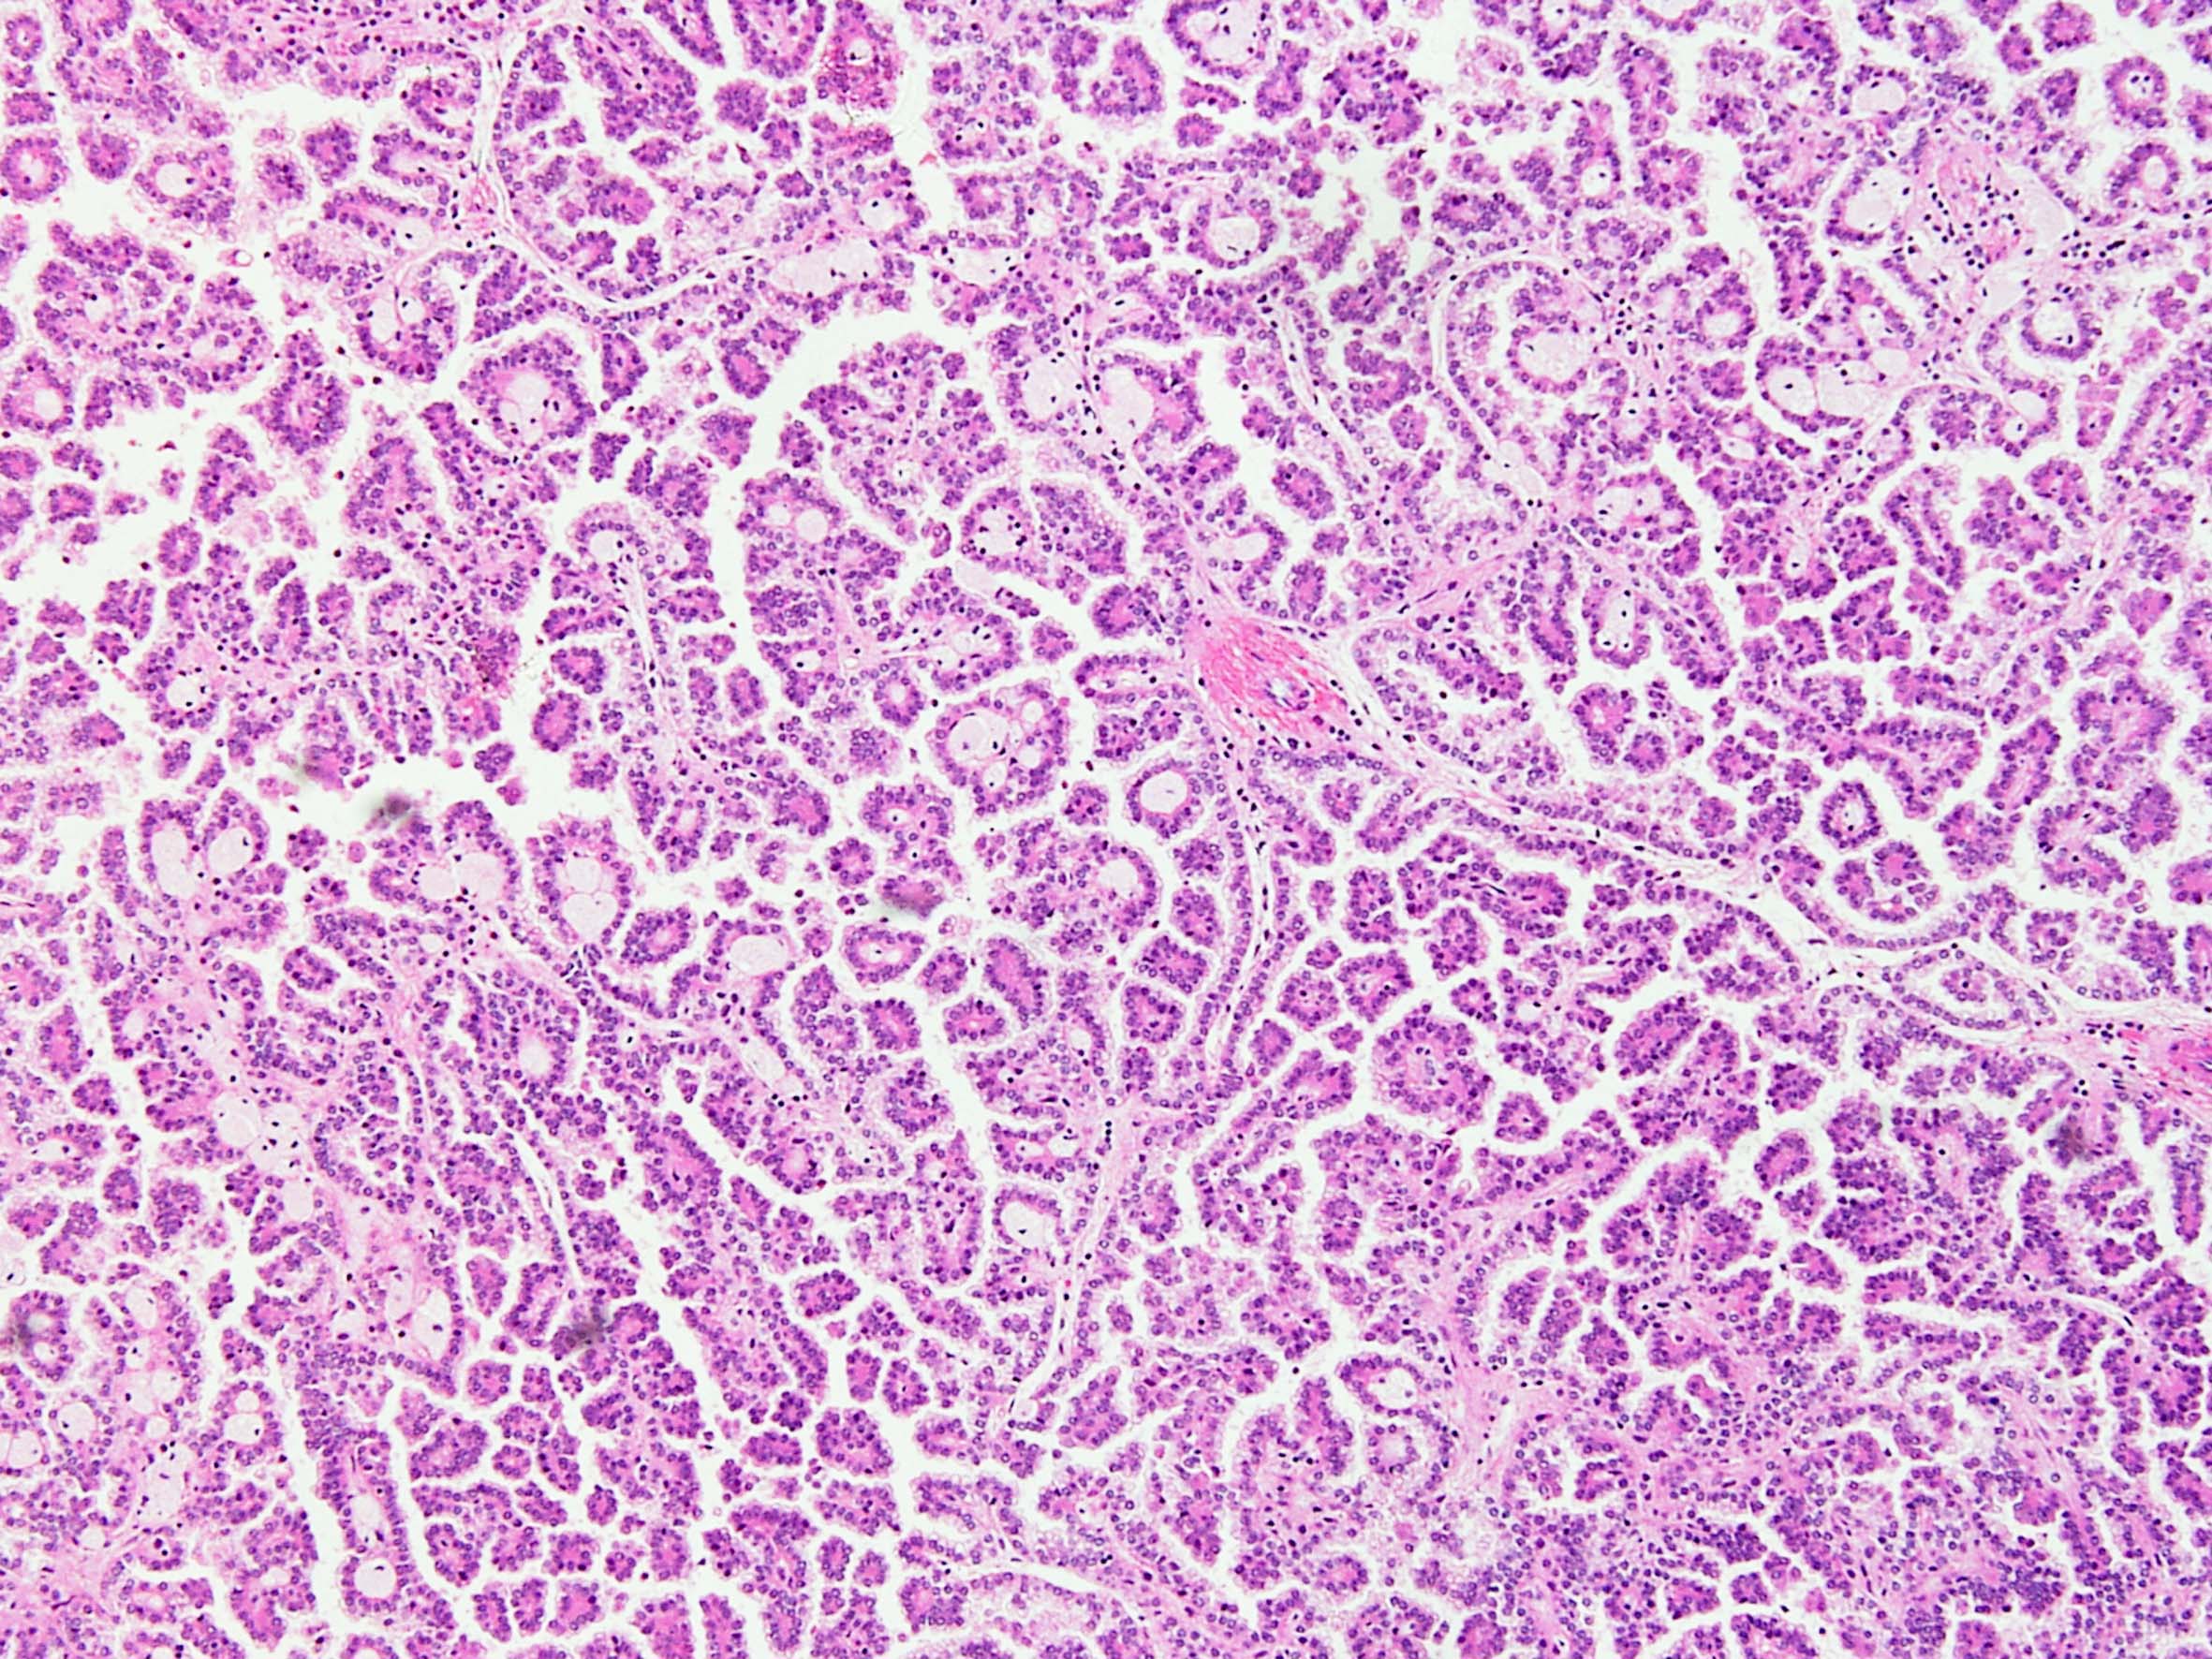

Classification of renal tumors

Case ID: 148